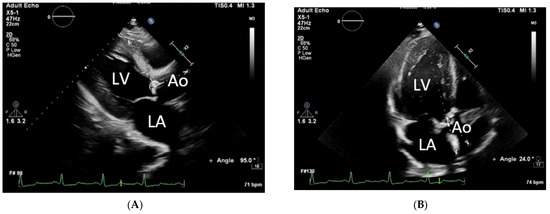

| Aortoseptal angle, ° | 124 [118; 132] | 114 [110; 117] | <0.001 * |

| Doppler intercept angle in A5C, ° | 18.8 [12.6; 26.0] | 30.6 [27.5; 34.6] | <0.001 * |